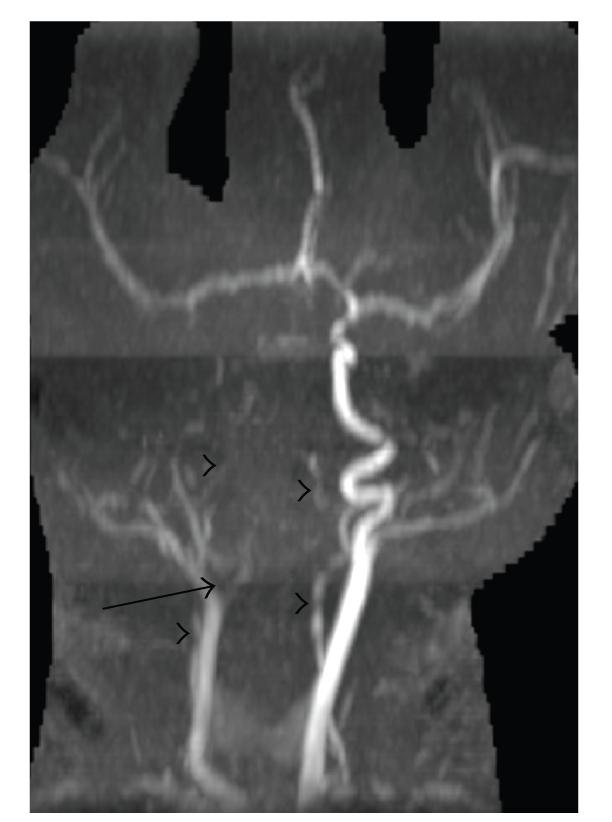

A full-term neonate suffered multifocal cerebral infarctions due to multiple large vessel thrombi. Thrombophilia and cardiovascular assessments were negative, but due to the severity of the lesions and the concern for expansion of the thrombi or future embolic events, treatment with low-molecular-weight heparin (LMWH) was initiated. No complications from treatment were experienced. We present this severe case in order to highlight difficult management decisions for newborns with multifocal perinatal thromboembolic stroke and to stress the need for further practice guidelines and research in this area.